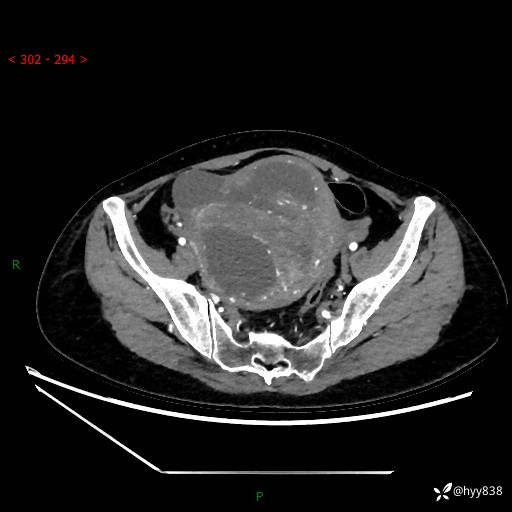

辅助检查:CT

增强(动脉期+静脉期)